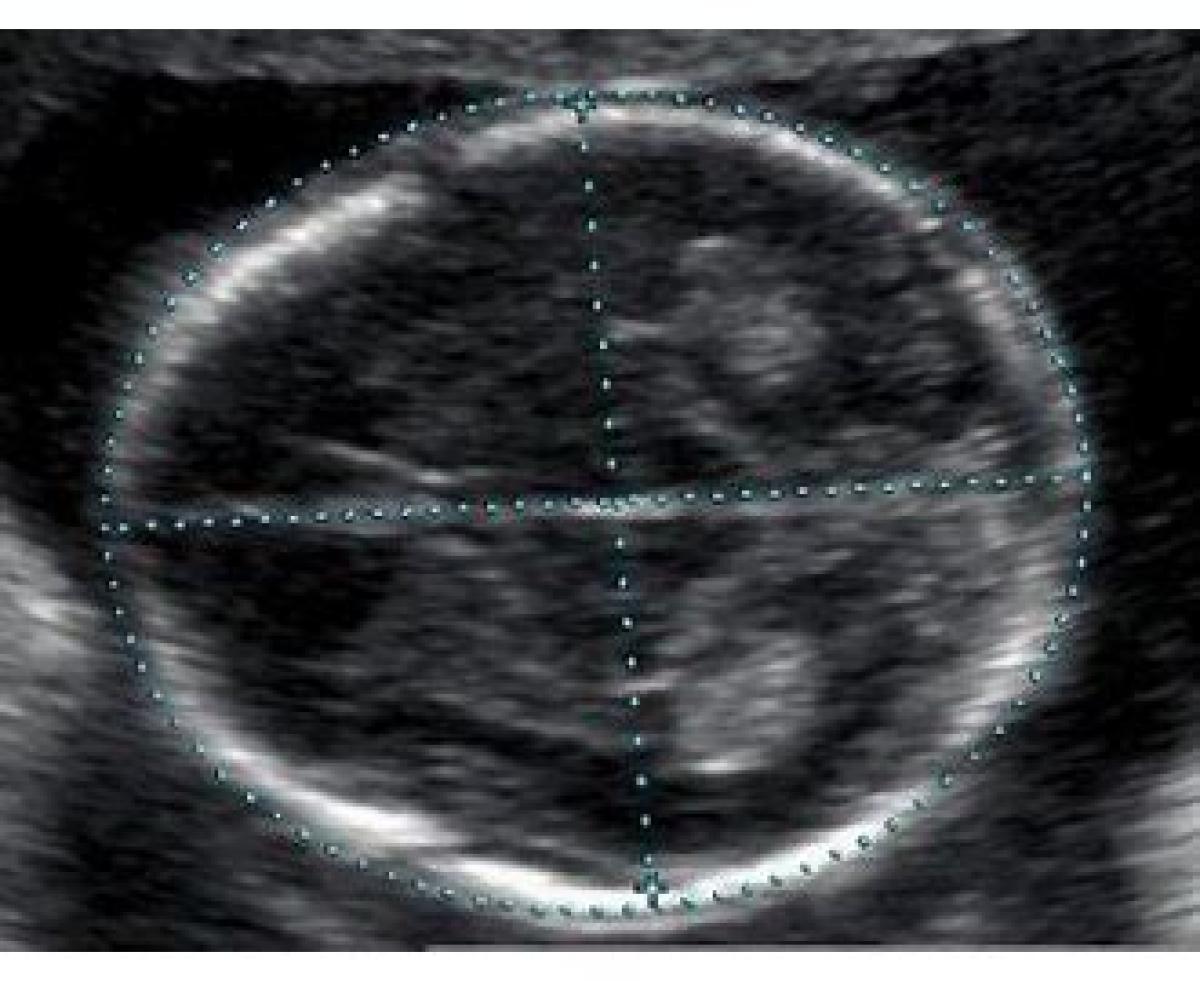

مخفف BPD

BiParietal Diameter

BPD به معنی قطر دوجداری است. این پارامتر اندازه بین دو طرف سر جنین را مشخص میکند و از هفته سیزدهم بارداری به بعد اندازه گیری می شود. مقدار آن از ۲٫۴ سانتیمتر در هفته سیزدهم تا ۹٫۵ سانتیمتر در انتهای بارداری تغییر میکند. البته جنین های مختلف اندازه سر متفاوتی دارند و تعیین زمان زایمان بر اساس این پارامتر دقیق و خیلی قابل اطمینان نخواهد بود.